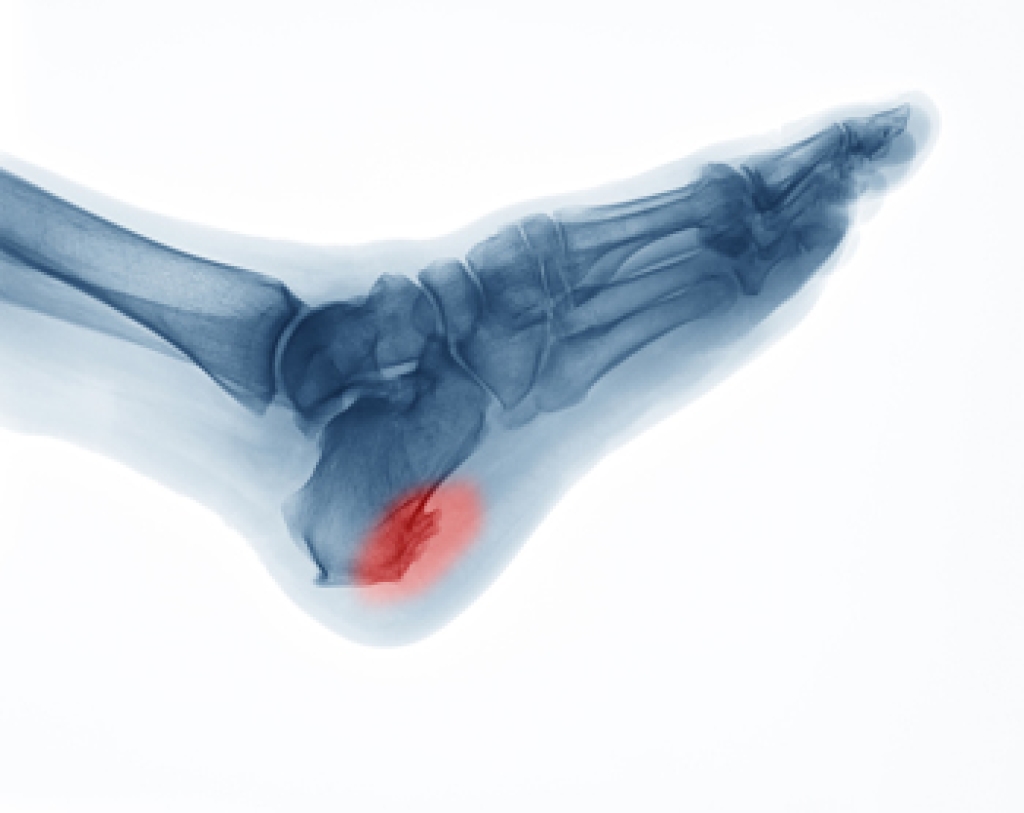

Those with diabetes are at serious risk due to being unable to feel an ulcer on their feet. Diabetics usually also suffer from poor blood circulation. This can lead to the wound not healing, infections occurring, and the limb may have to be amputated.

To treat neuropathy in the foot, podiatrists will first diagnose the cause of the neuropathy. Figuring out the underlying cause of the neuropathy will allow the podiatrist to prescribe the best treatment, whether it be caused by diabetes, toxic substance exposure, infection, etc. If the nerve has not died, then it’s possible that sensation may be able to return to the foot.

Pain medication may be issued for pain. Electrical nerve stimulation can be used to stimulate nerves. If the neuropathy is caused from pressure on the nerves, then surgery may be necessary.